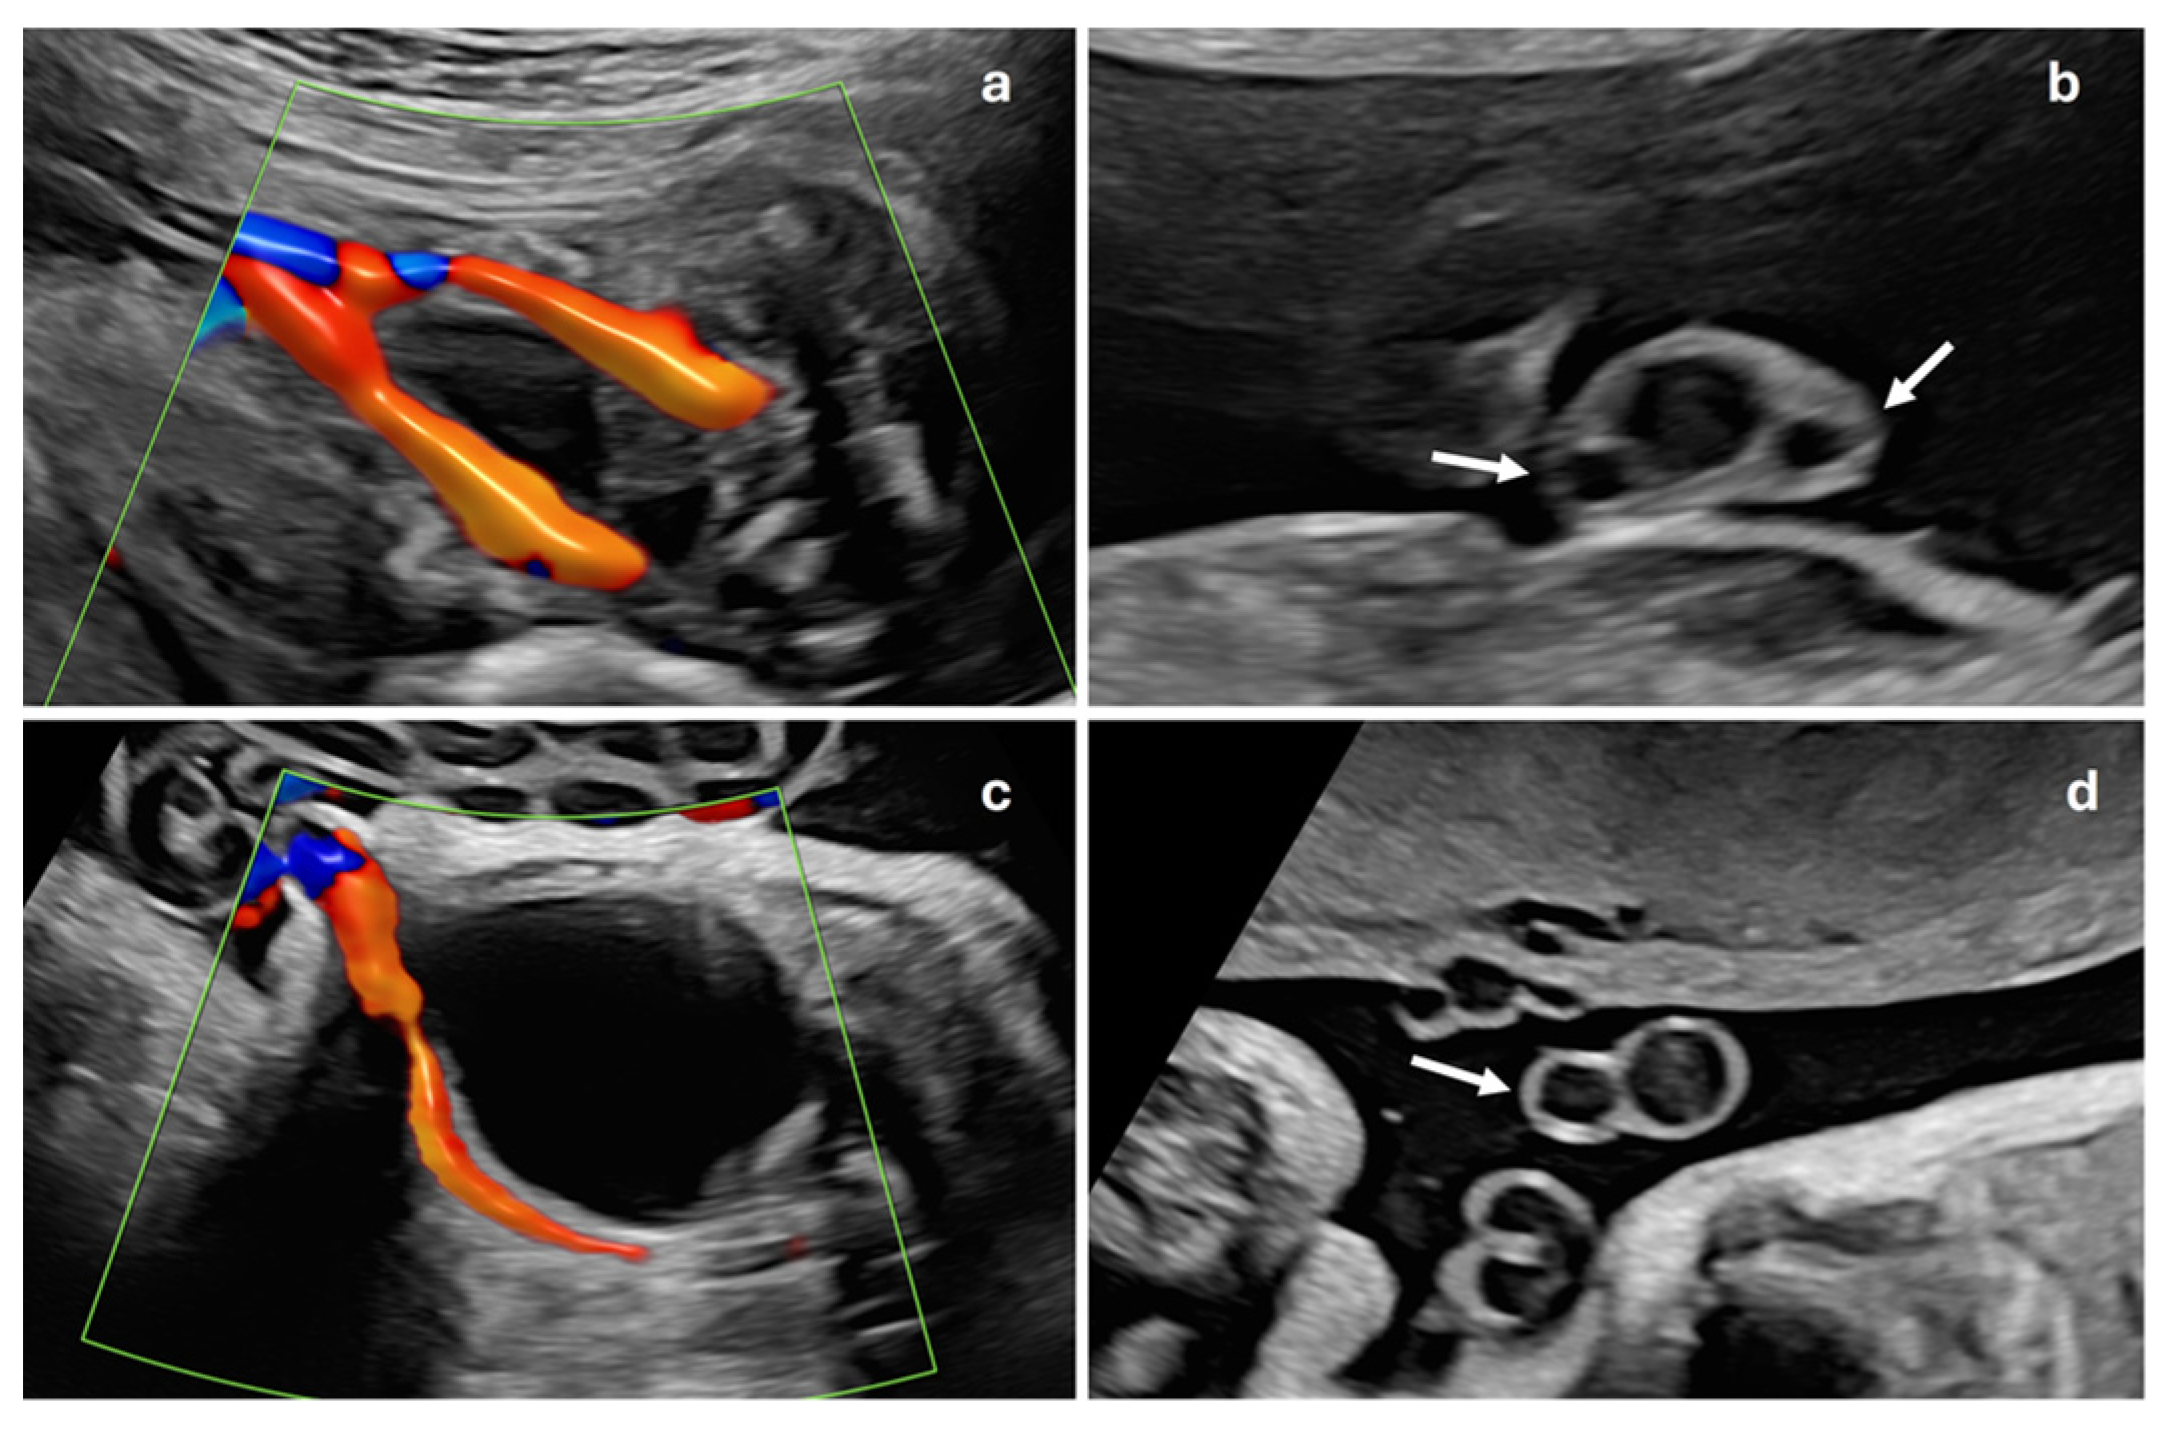

A prenatal examination of the umbilical cord is an essential part of the ultrasound scan in pregnancy. The presence of a single artery, known as a single umbilical artery (SUA) (Figure 1), is considered a risk marker for trisomy and may be associated with fetal malformations in up to 11–30% of cases [1,2,3]. When a single umbilical artery is observed without any other detectable malformations, it is termed isolated single umbilical artery (ISUA). The findings in existing studies are inconsistent: some studies report that the presence of SUA is linked to an increased risk of preterm birth and fetal growth restriction (FGR) and higher perinatal morbidity and mortality [2,4,5,6,7,8]. However, these associations have not been corroborated by other research [9,10], leading to conflicting conclusions regarding the implications of SUA.

This is a descriptive, observational and retrospective study with a total of 1157 consecutive singleton pregnant patients treated at the Department of Gynaecology and Obstetrics of the Hospital Universitario de Salamanca, during the period from 1 January to 31 August 2023. Inclusion criteria were women with singleton gestations without other associated ultrasound markers, nuchal translucency less than 3.5 mm and no fetal malformations. Exclusion criteria were multiple gestations or those that did not meet the inclusion criteria. These pregnancies were compared with 77 gestations with ISUA, whose data were collected during the years 2019 to 2023 at the same center, ISUA being defined as the presence of a single umbilical artery without any other ultrasound signs or markers or fetal malformations (Figure 2). All ultrasound examinations were performed by one of the five specialists belonging to the Prenatal Diagnosis Department at the 20th-week ultrasound scan (AMC, MOMR, PO, AVY, FJG), following the ISUOG Protocol for the performance of the routine mid-trimester fetal ultrasound scan [11]. Once ISUA was diagnosed, it was confirmed by another of these specialists in the department at a subsequent visit. This study was approved by the Hospital Ethics Committee. Considering that this was a retrospective study, no informed consent was needed from the patients to carry out this study. Sample size was calculated using the WinEpi calculator (http://www.winepi.net/f102.php, accessed on 1 June 2022), considering a prevalence of 1% for ISUA [8] with a confidence level of 95%. Data were collected in a database created specifically for this study with Microsoft Excel (Microsoft Corporation, Redmond, WA, USA), which was accessible from the outpatient clinic, the delivery room and the hospital ward.

Figure 1. Prenatal ultrasound examination of the umbilical cord. Normal fetal umbilical cord in color Doppler mode (a), showing two umbilical arteries passing on either side of fetal bladder, and in grayscale transverse section (b), where two umbilical arteries (white arrows) and umbilical vein are visible, confirming three-vessel cord. Fetal umbilical cord with single umbilical artery in color Doppler mode (c), demonstrating only one umbilical artery adjacent to fetal bladder, and in grayscale transverse section (d), showing single artery (white arrow) and one umbilical vein, indicating two-vessel cord.